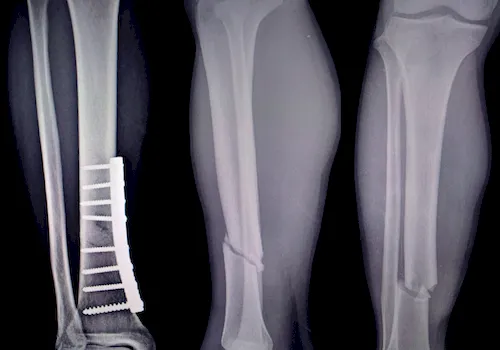

| ▸ | Röntgen Erkennung von Knochenbrüchen (zuverlässige Ergebnisse erst im späteren Krankheitsverlauf – neue, starke Rückenschmerzen; chronische Rückenschmerzen unbekannter Ursache; hohes Lebensalter; niedrige Knochendichte; mehrere, alte Brüche; Größenverlust von > 5 cm seit 25. Lebensjahr und > 2 cm bei Kontrolluntersuchungen) |

| ▸ | Computertomografie (CT), Magnetresonanztomografie (MRT) Erkennung von frischer oder verheilter Fraktur und genaue Auswertung der Frakturmorphologie |

Röntgenaufnahmen von verschiedenen Knochenbrüchen bei Osteoporose

Diese Diagnostikmethoden kombiniert sind von großer Bedeutung, um individuelle Risikoprofile zu erstellen und eine präzise Behandlung einzuleiten. Eine frühzeitige Untersuchung ermöglicht es Ihnen, gezielt Maßnahmen zu ergreifen und so die Stabilität Ihres Knochengerüsts langfristig zu sichern.